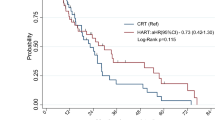

The median follow-up times for the hypo-IMRT/TMZ alone trial and the hypo-IMRT/TMZ/BEV trial were 13.9 and 14.7 months, respectively. Median PFS was increased by 3.4 months in the hypo-IMRT/TMZ/BEV trial, compared to the hypo-IMRT/TMZ alone trial (12.8 vs. 9.4 months, p = 0.58) (Fig. 1). PFS at 6 months was not significantly different between the two trials (84 and 83 %, respectively, p = 0.702). Median OS was the same in both trials at 16.3 months (Fig. 2).

In the hypo-IMRT/TMZ/BEV trial we sought to evaluate the effect of bevacizumab in combination with hypo-IMRT and temozolomide on PFS survival as a primary endpoint, and OS and toxicity as secondary endpoints. This comparison study demonstrated a statistically non-significant increase in PFS with bevacizumab of 3.4 months (p = 0.39), and no difference in OS. Two recently published large randomized trials, the AVAGlio and RTOG 0825, have reported similar findings with standard fractionation radiation, temozolomide and BEV. The addition of bevacizumab improved progression free survival by 3.4–4.4 months, but had no effect on OS [22, 23].